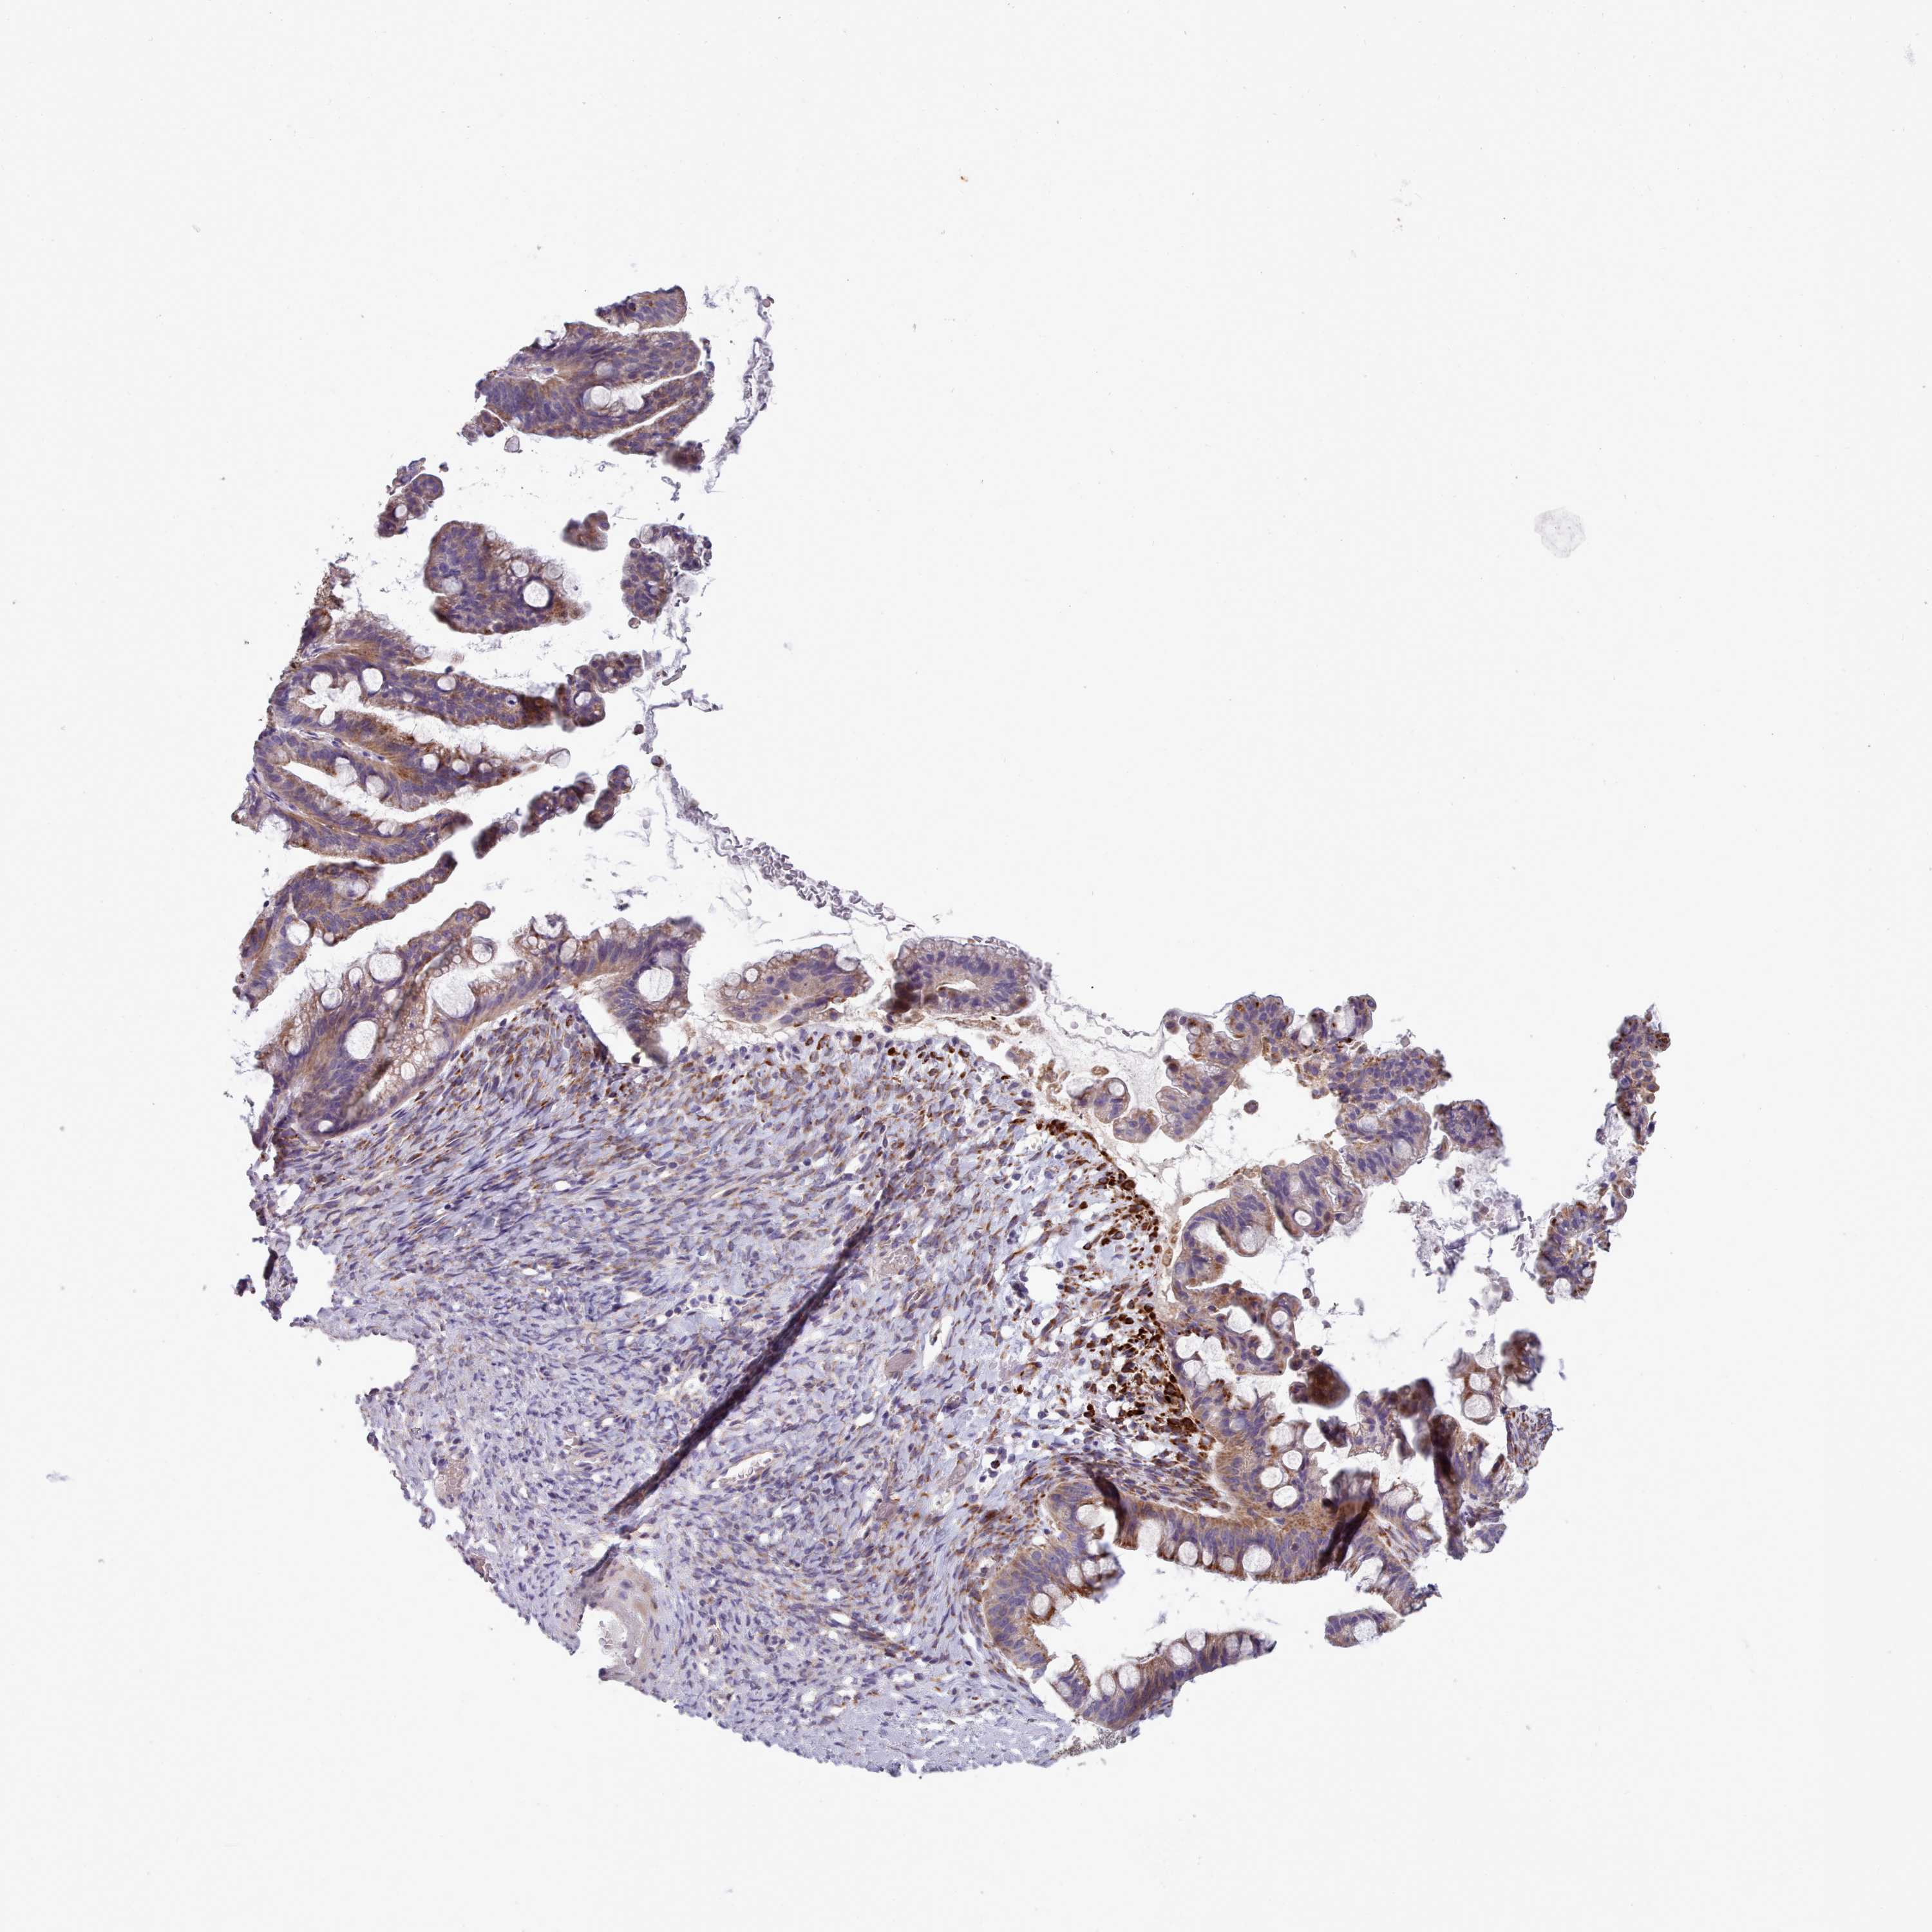

OVARIAN CANCER - Protein expressioni

A mouse-over function shows sample information and annotation data. Click on an image to view it in a full screen mode. Samples can be filtered based on level of antibody staining by selecting one or several of the following categories: high, medium, low and not detected. The assay and annotation is described here.

Note that samples used for immunohistochemistry by the Human Protein Atlas do not correspond to samples in the TCGA dataset.

Antibody stainingi

Antibody staining in the annotated cell types in the current human tissue is reported as not detected, low, medium, or high, based on conventional immunohistochemistry profiling in selected tissues. This score is based on the combination of the staining intensity and fraction of stained cells.

Each image is clickable and will lead to virtual microscopy that enables deeper exploration of all samples and also displays staining intensity scores, fraction scores and subcellular localization as well as patient and tissue information for each sample.

Antibody HPA051171

Antibody HPA057021

Cystadenocarcinoma, serous, NOS

Carcinoma, NOS

Cystadenocarcinoma, mucinous, NOS

Carcinoma, endometroid